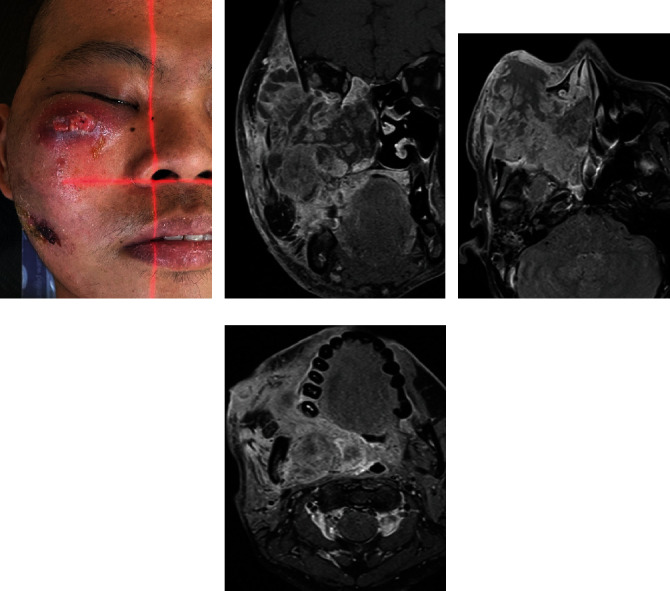

Sinonasal malignancies (SNMs) are rare heterogeneous malignancies that frequently present with locally advanced disease. The prognosis is poor when the disease is considered extensive and unresectable. In such cases, a high-dose palliative radiotherapy regimen is often required, but the ideal dose and fractionation have not been established. We detail a 33-year-old male who initially presented with a progressively growing mass over the right cheek. A biopsy of the lesion revealed squamous cell carcinoma (SCC). Imaging revealed a very advanced and unresectable disease with the involvement of several head and neck subsites. He progressed further after receiving induction chemotherapy from an outside institution. The patient requested prompt tumor and symptom control to travel back to his home country. We offered him high-dose split-course palliative radiotherapy in the form of a quad Shot of 14.80 Gy in four fractions twice daily, followed by 30 Gy in five fractions every other day with a 2-week interval. Treatment resulted in excellent clinical response with symptomatic relief in a short time, and the patient could travel back home safely.